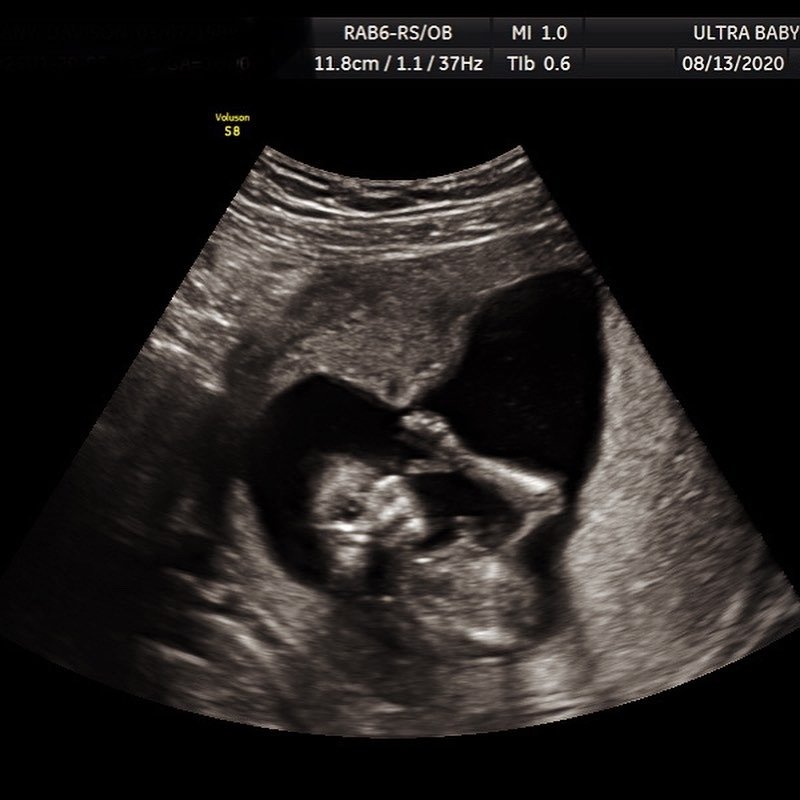

Can I see my baby’s face clearly in a 4D ultrasound?

Yes, 4D ultrasound can show real-time facial expressions and movements, depending on the baby’s position and amniotic fluid available.